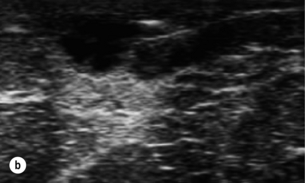

Due to the difficulty of predicting the presence of pus within an inflamed breast, ultrasound with or without aspiration should be performed.71 The need for open drainage in breast abscesses has been superseded by the use of aspiration.7274

This has allowed management of breast infection to become outpatient based. Protocols validated within the Edinburgh Breast Unit have demonstrated that few if any breast abscesses require incision and drainage under general anaesthesia.75 All abscesses should be assessed by ultrasound and if pus is present the surgeon or radiologist aspirates this, usually under ultrasound guidance (Figs 17.8 and 17.9). Patients are reviewed every 2–3 days and any further collections aspirated until no further pus forms. Drainage of pus by making a small stab incision in the skin under local anaesthesia is performed in patients where the overlying skin is thinned or necrotic (Fig. 17.10). The incision to drain any breast abscess should be just large enough to allow the pus to drain (1 cm or less), which minimises later scarring. Ultrasound provides a simple method for differentiating an abscess from cellulitis, allows assessment of any loculation, which is rare, and permits complete aspiration of all pus. Experience in the Edinburgh Breast Unit of using ultrasound to assist aspiration of breast abscesses is that it is quick and simple to learn and use. Local anaesthetic (1% lignocaine with 1:200 000 adrenaline) is injected into non-inflamed skin away from the abscess and along the needle track and is then irrigated into the abscess cavity. Aspiration is then relatively painless and the local anaesthetic helps if the pus is thick by diluting the pus to allow aspiration. Periareolar non-lactational abscesses can be treated and cured by repeated aspiration. Due to the recurrent nature of periareolar infection, recurrent abscess formation is common and in such patients when all signs of acute infection have settled, which takes at least 6 weeks, careful surgical excision of any residual abscess and affected ducts is often required. A mammary duct fistula (a connection between the infected and damaged duct and the skin, usually at the edge of the areola) develops in up to one-third of patients after incision and drainage of a periareolar abscess.76 Fistulas require definitive surgical management. Options include fistulotomy, cutting down on a probe into the fistula and allowing healing by secondary intention, which is painful after surgery and produces an ugly scar, and fistula excision and primary closure. Excising a fistula is easier through a radial scar, but circumareolar incision produces the best cosmetic outcome. Complete excision of the granulation tissue lined tract (plus the affected ducts under the nipple) and primary closure requires antibiotic cover (Fig. 17.11). There is a high risk of recurrence in the presence of postoperative wound infection.77

image

Figure 17.8 Aspiration of abscesses under ultrasound guidance. (a) Ultrasound view of a breast abscess. (b) The needle can be seen entering the abscess on the right, allowing aspiration to be performed.